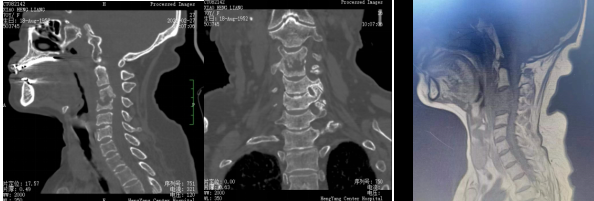

患者入院后完善相關(guān)檢查,不查不知道,一查不簡單:患者頸椎疼痛不是簡單的肌肉勞損,而是頸椎骨頭出現(xiàn)了破壞、塌陷,神經(jīng)受壓。由于患者頸椎病變位置較高,骨質(zhì)破壞范圍較大,并后凸、脊髓受壓,椎體穩(wěn)定性差,稍有不慎容易出現(xiàn)災(zāi)難性后果?,F(xiàn)有的重建材料難以達(dá)到好的臨床效果,蘇光輝主任團(tuán)隊采用先進(jìn)的3D打印技術(shù),為患者進(jìn)行了個性化手術(shù)方案及假體設(shè)計,假體與需要切除骨質(zhì)完美匹配,最大程度恢復(fù)解剖結(jié)構(gòu)及重建的穩(wěn)定性,對假體進(jìn)行骨小梁結(jié)構(gòu)設(shè)計,具有良好的骨長入效果,能夠減少假體下沉及松脫等術(shù)后并發(fā)癥的發(fā)生。

術(shù)前影像:C3、4椎體病變,椎管狹窄